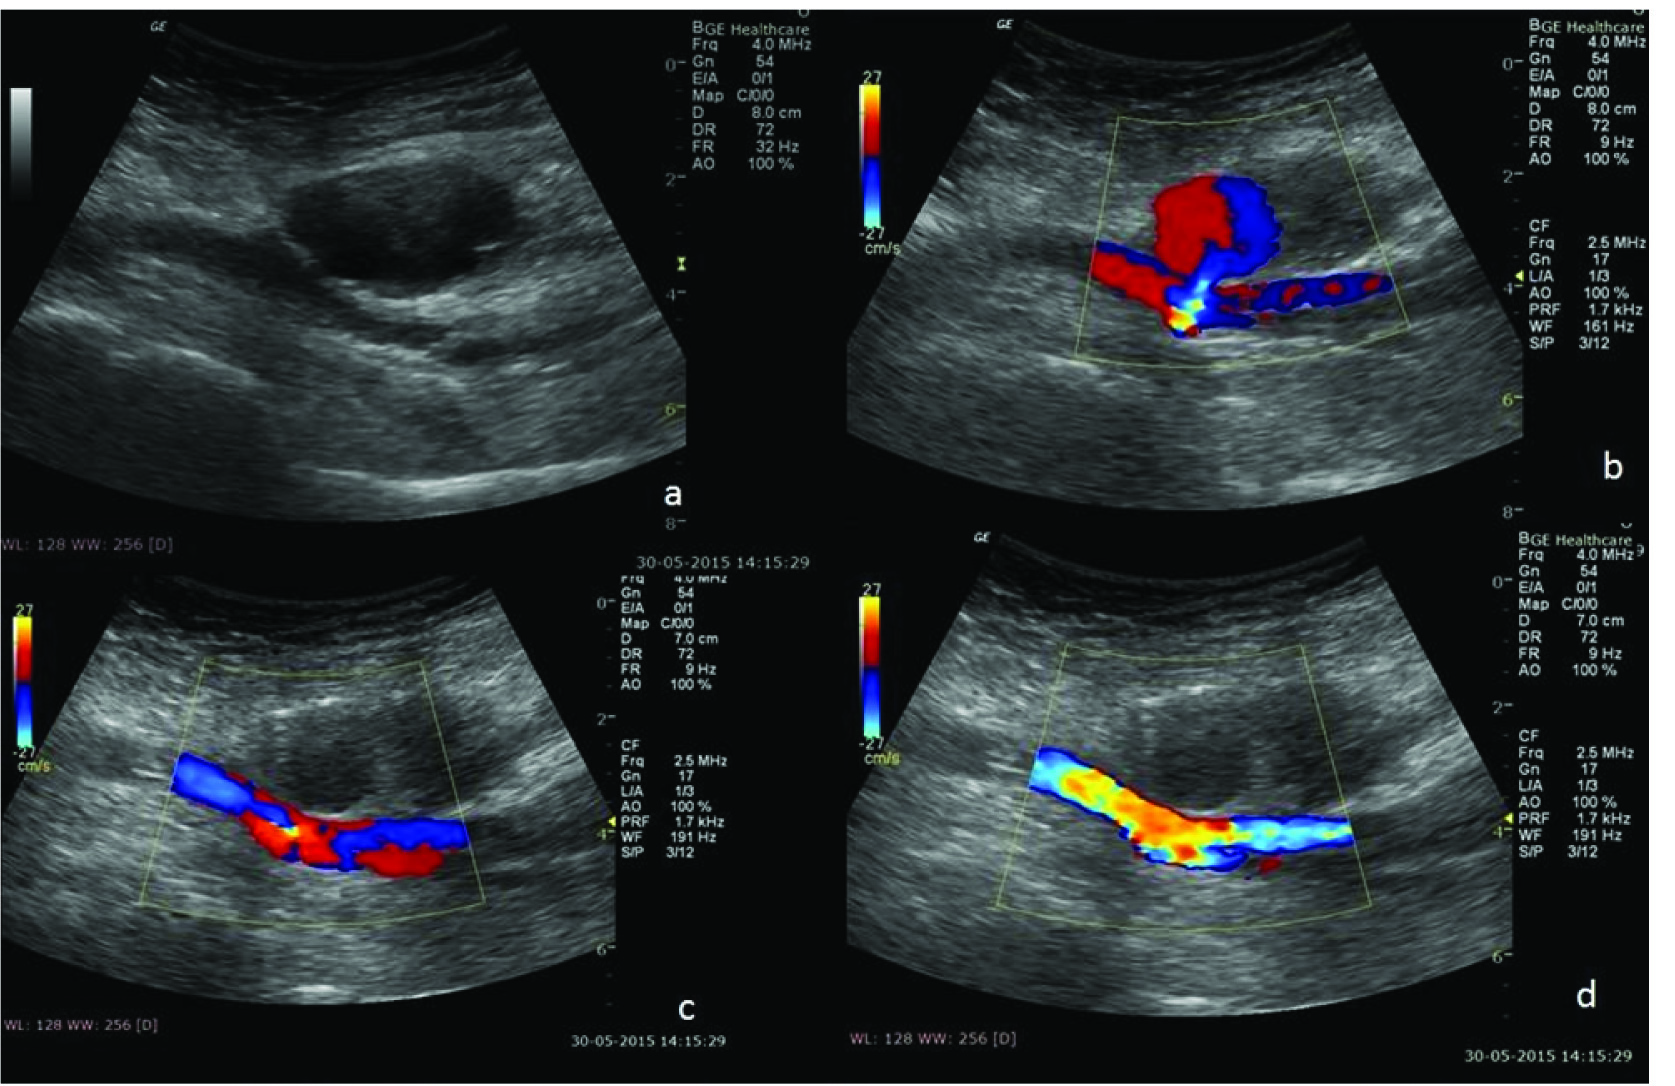

(a) Doppler image shows pseudoaneurysm communicating with underlying femoral artery; (b) Needle is then advanced inside the sac; Post thrombin injection images; (c,d) showing increased echogenicity inside the pseudoaneurysm (due to thrombus formation) and no flow within.

B-mode (a) and Doppler images (b) showing pseudoaneurysm communicating with underlying femoral artery. Post procedure images (c, d) showing increased echogenicity inside the pseudoaneurysm (due to thrombus formation) and no flow within.